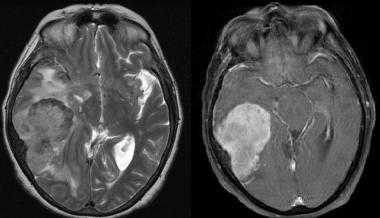

Менингиома височной области. На серии последовательных МР-изображений видно крупное образование правой височной области с паттерном контрастирования по типу «колеса со спицами», местным объемным воздействием, отеком окружающих тканей и гиперостозом подлежащей кости.